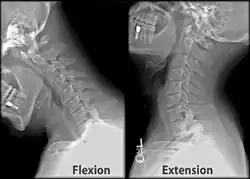

X-ray of cervical spine (neck) in flexion and extension (bending backwards)